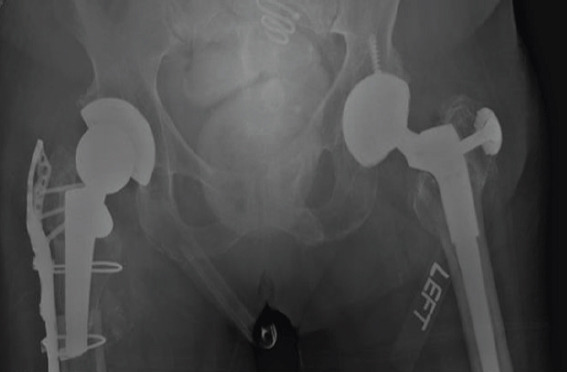

Case report: An 88-year-old female with multiple comorbidities, including osteoporosis and a history of bisphosphonate therapy, presented with an APFF of the right femur following a ground-level fall. One year prior, she had undergone uncomplicated THA with a long cylindrical, fully porous-coated femoral stem. Radiographs revealed a transverse fracture at the subtrochanteric region, lateral cortical thickening, and femoral stem breakage. Given the patient's medical history and the complexity of the fracture, revision surgery was indicated. Surgical intervention included the preservation of the proximal femoral stem and the removal of the distal stem segment, combined with periprosthetic plate fixation and cortical strut allograft for stabilization.